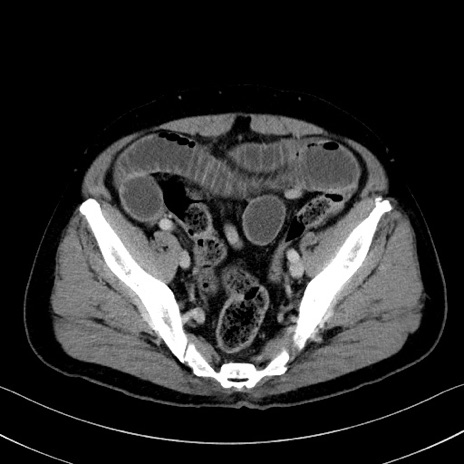

症例35(横断像)

【症例】70歳代 男性

【主訴】腹部膨満、嘔吐

【現病歴】昨日より腹部膨満感出現。本日増悪し、仙痛出現。嘔吐あり、受診。

【既往歴】糖尿病、胆摘後

【身体所見】BP 149/80mmHg、HR 74/min、BT 35.9℃、腹部:膨満、軟、圧痛なし。腸雑音減弱あり。上腹部正中切開瘢痕あり。

【データ】WBC 13500、CRP 1.72